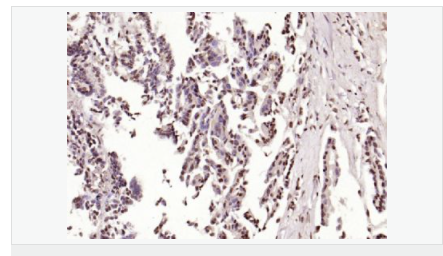

交叉反應(yīng):Human,Mouse,Rat(predicted:Dog,Pig,Rabbit,GuineaPig) 推薦應(yīng)用:IHC-P,IHC-F,ICC,IF,Flow-Cyt,ELISA

| 英文名稱 | phospho-HSP70 (Tyr611) |

| 中文名稱 | 磷酸化熱休克蛋白-70抗體 |

| 產(chǎn)品類型 | 磷酸化抗體 |

| 交叉反應(yīng) | Human, Mouse, Rat, (predicted: Dog, Pig, Rabbit, Guinea Pig, ) |

| 產(chǎn)品應(yīng)用 | ELISA=1:5000-10000 IHC-P=1:100-500 IHC-F=1:100-500 Flow-Cyt=1μg/Test ICC=1:100 IF=1:100-500 (石蠟切片需做抗原修復(fù)) not yet tested in other applications. optimal dilutions/concentrations should be determined by the end user. |

| 免 疫 原 | KLH conjugated Synthesised phosphopeptide derived from human HSP70 around the phosphorylation site of Tyr41:GL(p-Y)QG |